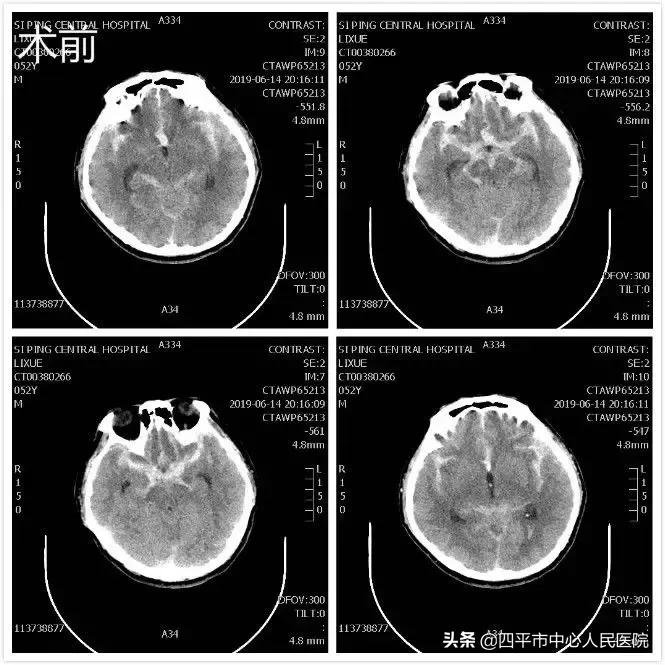

Case1 左侧颈内动脉末端囊状动脉瘤

患者刘XX,缘于入院前2小时无明显诱因在劳动时突发意识不清,从2米高处坠落,既往身体健康,入院头部CT提示蛛网膜下腔出血,李晓东主任阅头部CT片后指示该患者应该是先脑出血而后摔倒,不能除外动脉瘤破裂,入院后完善头部CTA检查,提示1.左侧颈内动脉末端动脉瘤。2.左侧大脑中动脉闭塞。3.双侧颈内动脉颅内段轻度狭窄。4.脑内动脉粥样硬化改变。5.右侧胚胎型大脑后动脉。李晓东主任带领孙庆华急诊全麻下行左侧颈内动脉末端动脉瘤夹闭术,术中注意避免误夹后交通动脉,否则造成的后果是灾难性的,经术中仔细操作,确切夹闭动脉瘤,术中顺利,术后患者病情逐渐好转,出院时神清语明,四肢肌力5级,送来锦旗表示感谢。